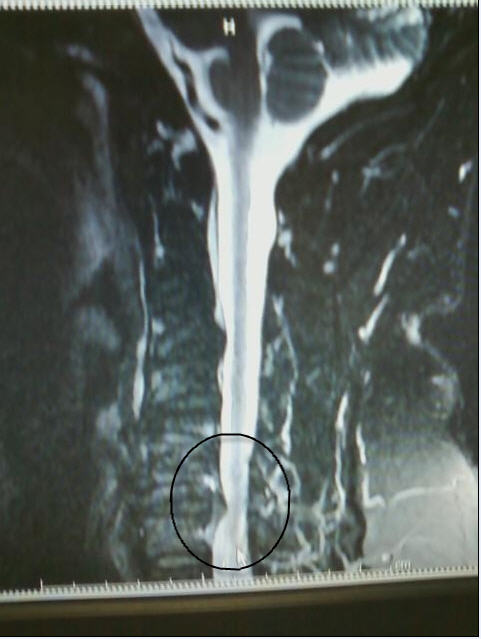

I know this is bordering on TMI, but if you have ever wondered what your spine should NOT look like....

Attached Images

File Type: jpg MRI2.jpg (41.4 KB, 297 views)